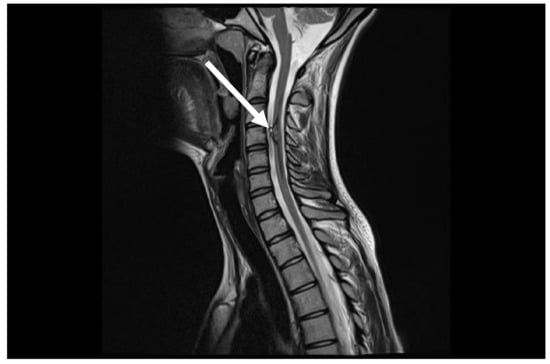

7.1. First Episode (2011)

7.2. Second Episode (2020)

7.3. Third Episode (2023)